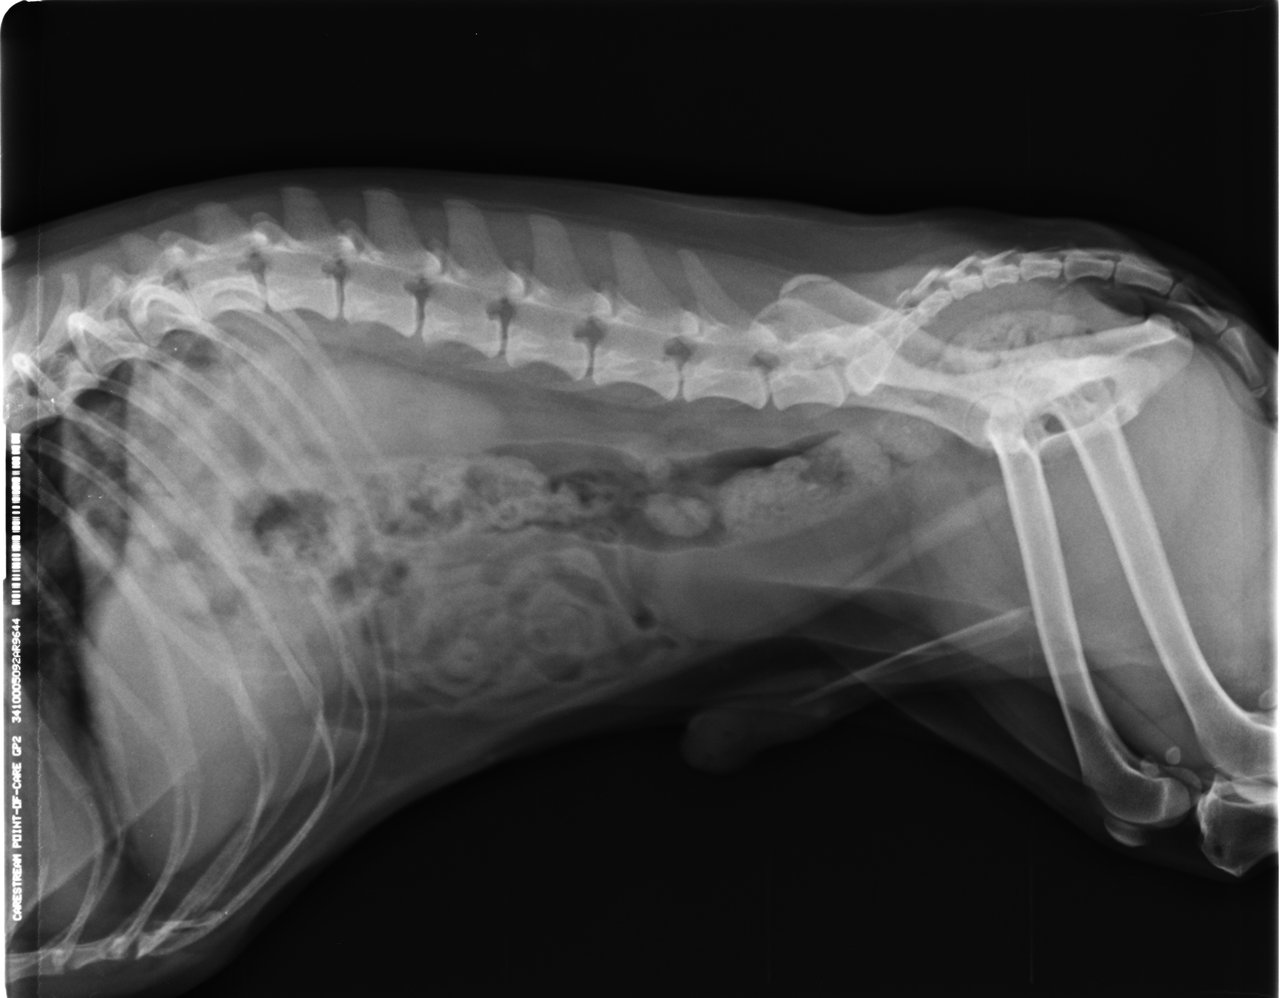

3歳の時、椎間板ヘルニアで手術し、

予備軍を抱えているだいもん部長。

麻痺はなく炎症のみでなんとか踏ん張っているものの、